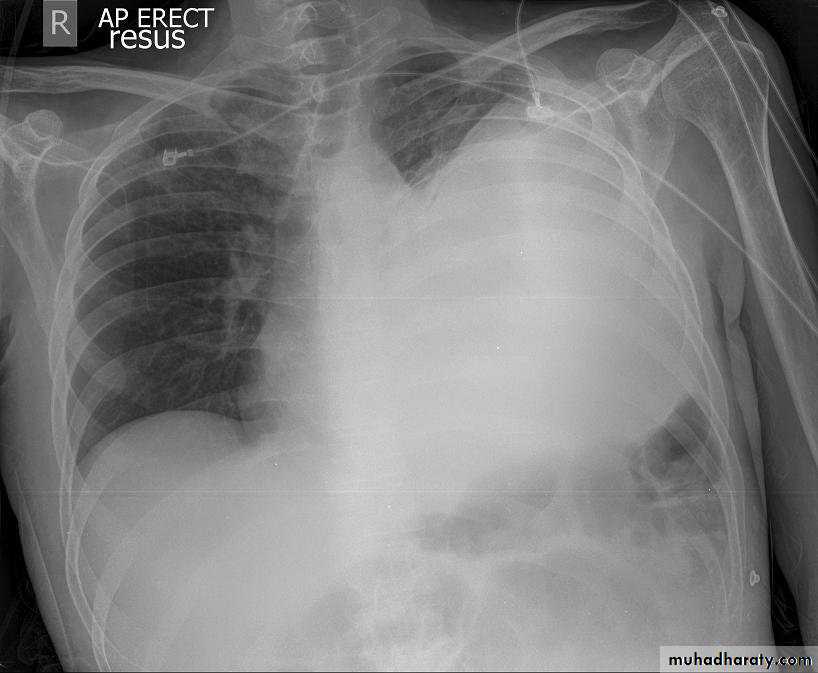

1-CXR:

PA and lateral views show effusion, air fluid level

CXR : Air fluid level is only seen in upright filmCT san : clarify the diagnosis when the CXR is equivocal